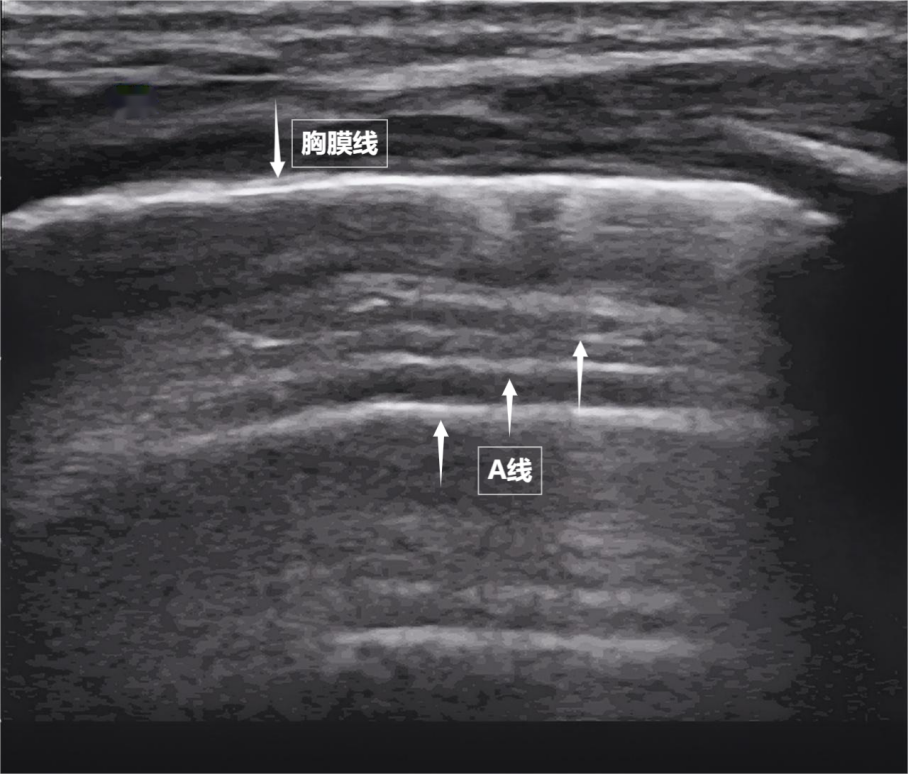

第一景:“海岸線與海浪”——胸膜線與A線

當聲波穿過胸壁肋骨縫隙,首先會遇到緊貼肺表面的光滑薄膜——壁層胸膜和臟層胸膜。兩者緊密相貼,中間沒有多余的氣體或液體。它們在屏幕上呈現(xiàn)為一條明亮、光滑的水平線,共同構成了胸膜線。這條線就是肺的“海岸線”。在它的下方,由于肺泡內(nèi)大量氣體對聲波的強烈反射,會出現(xiàn)一系列與胸膜線平行的、等間距的、重復出現(xiàn)的明亮平行線,像海浪般不斷向屏幕深處延伸,這就是A線(見下圖)。A線是正常含氣肺部的典型標志。它的存在直接提示肺表面含氣充足,胸膜腔內(nèi)無異常積液或氣體。

圖為正常新生兒肺部超聲表現(xiàn)